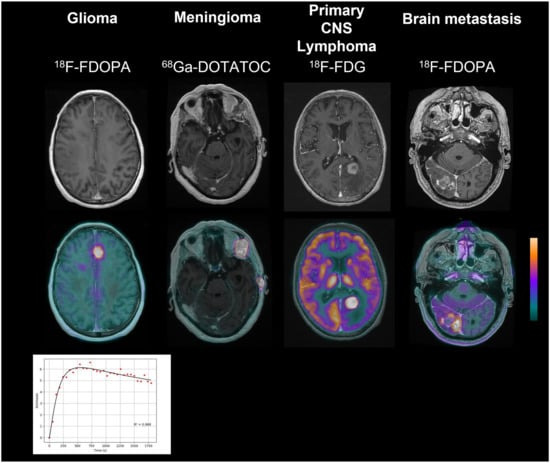

2.1. Glioma

2.2. Meningioma

2.3. Primary CNS Lymphoma

2.4. Brain Metastases